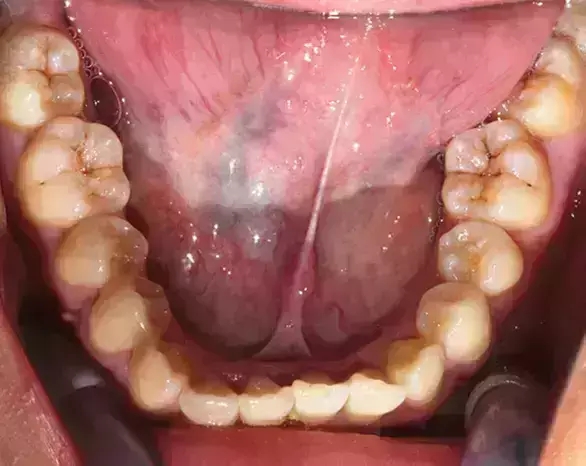

Damon 病例分享:安氏 II 類二分類露齦笑的矯治(董一磊)

患者信息